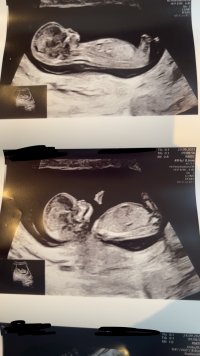

Hei! Nylig vært på tidlig offentlig ultralyd. Hvor jordmor tippet på jente, men kunne ikke garantere. Noen som tørr å gjette?